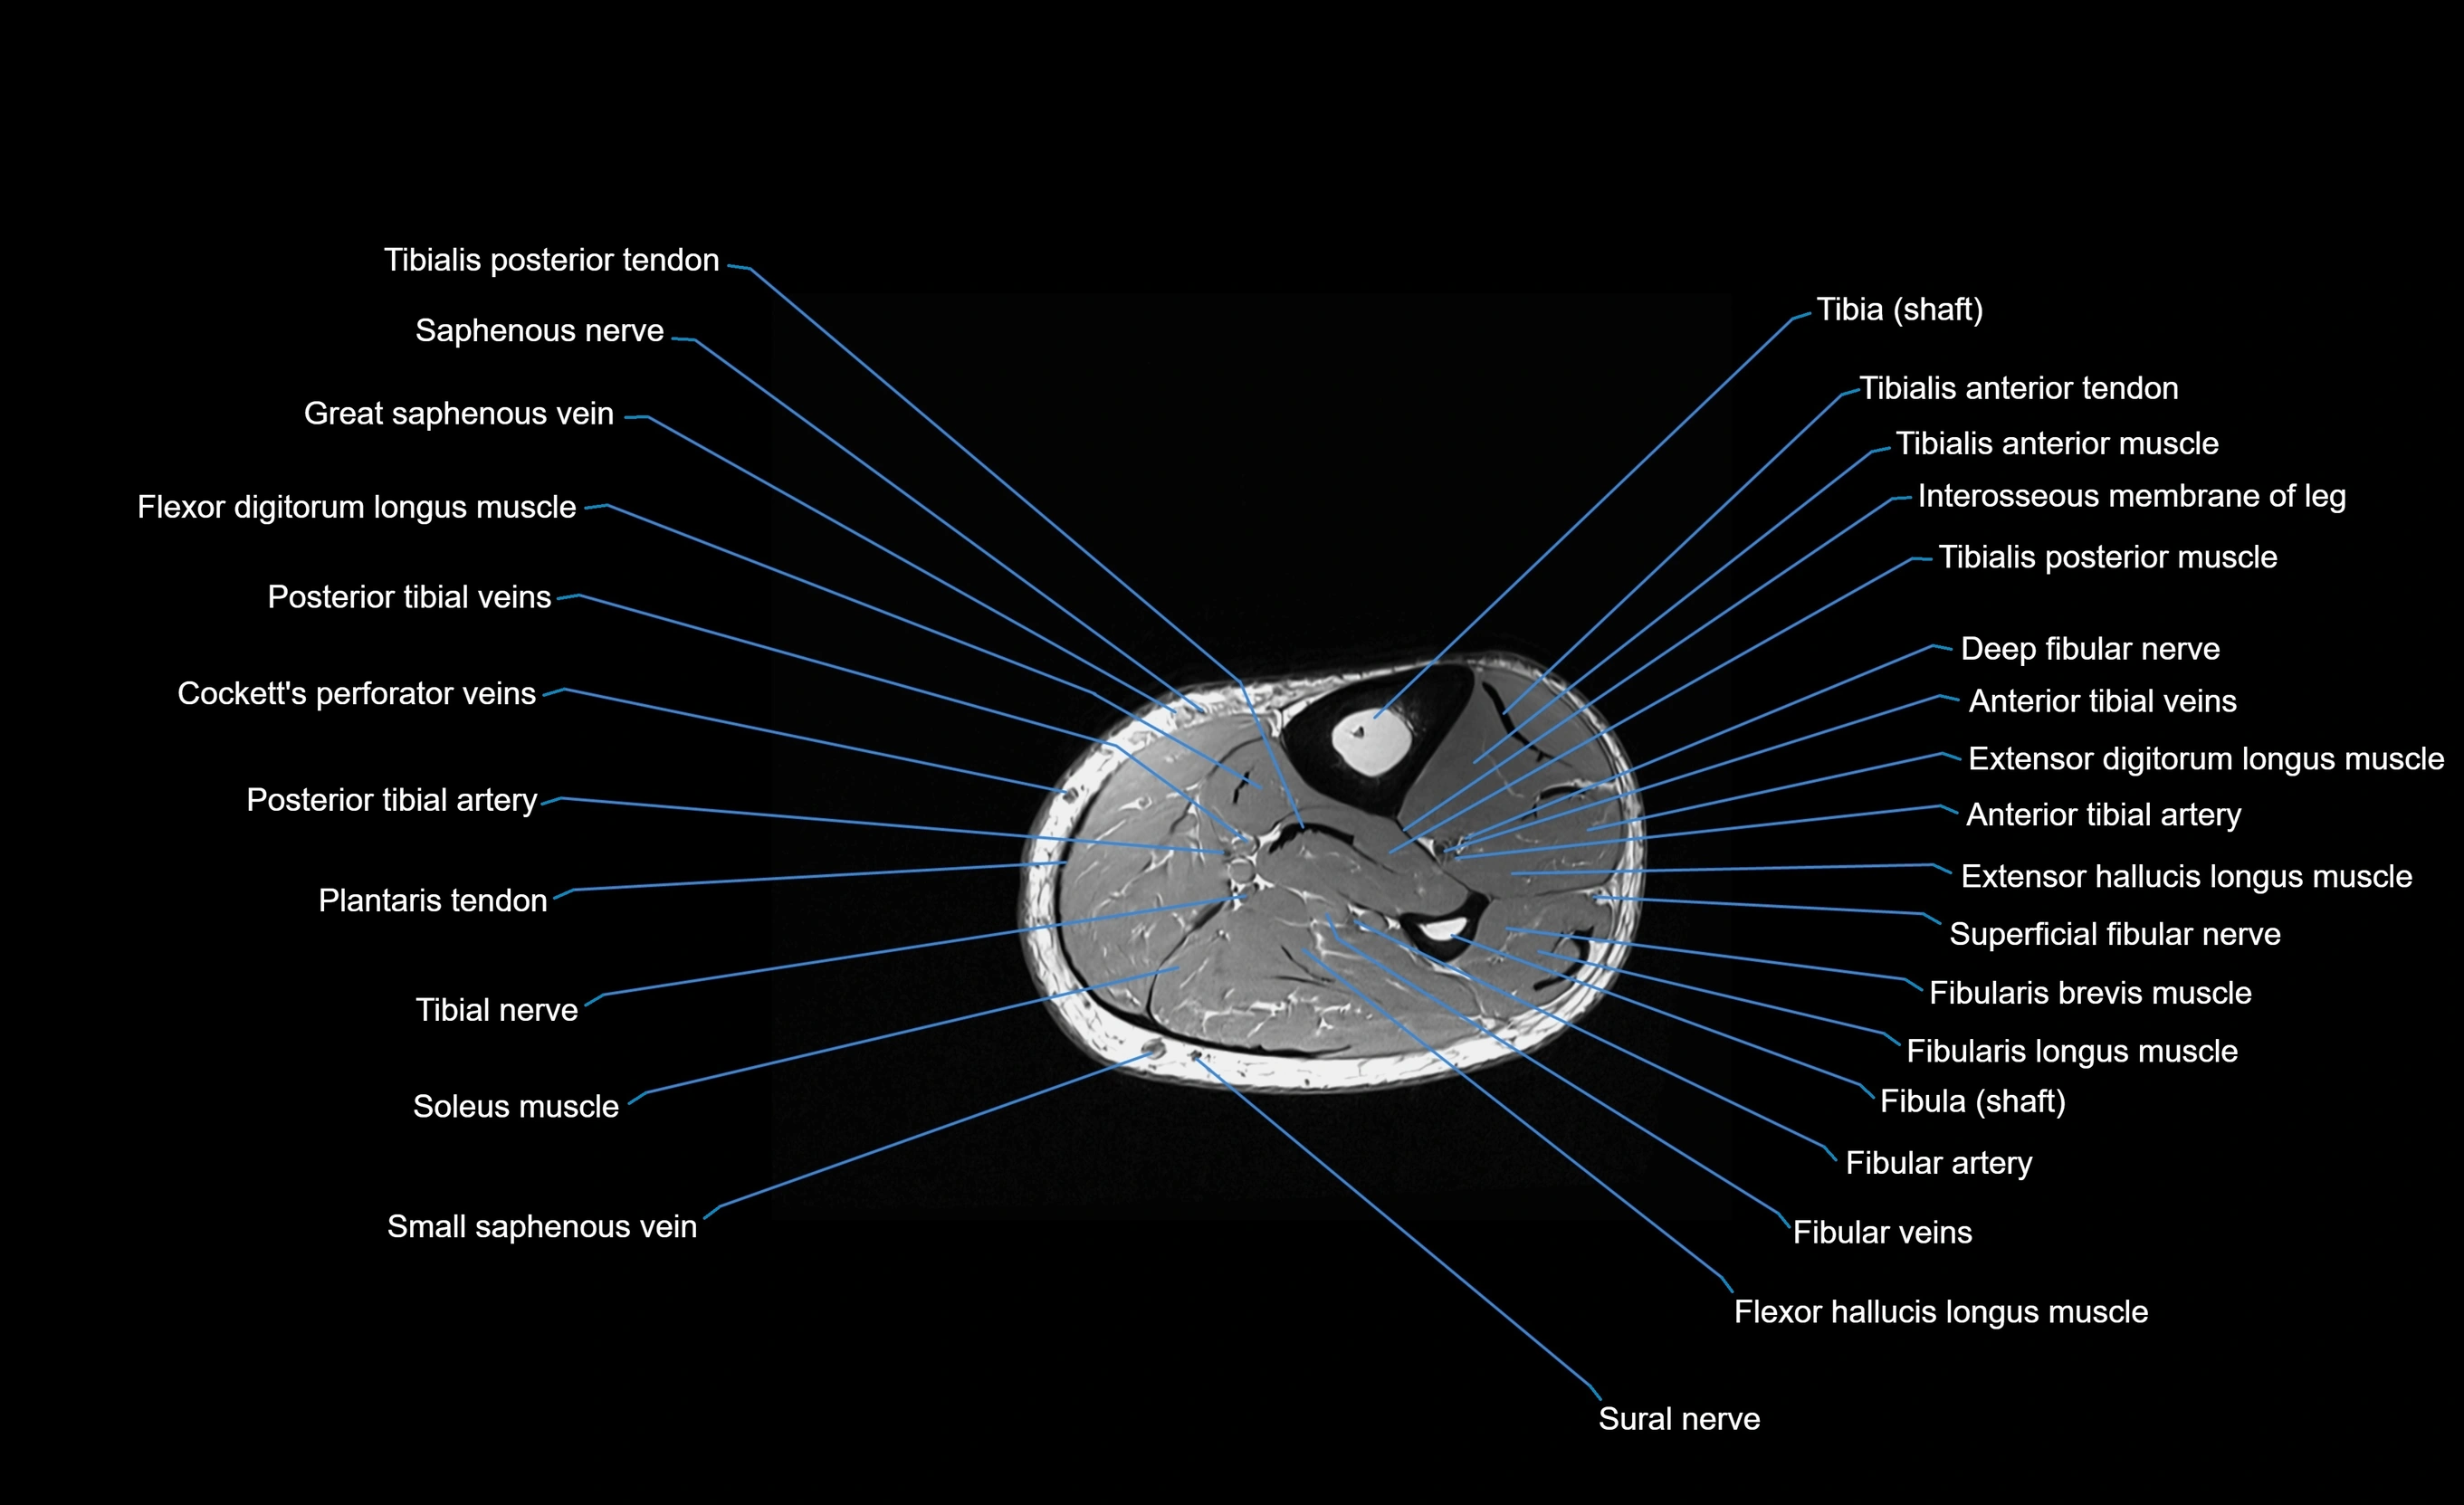

MRI image